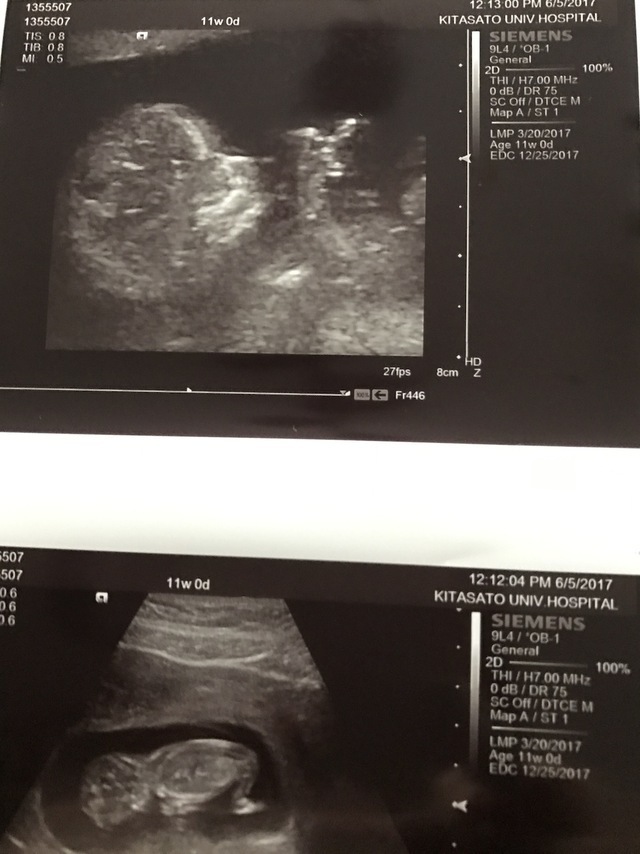

11週0日(11w0d・女の子)|pon2019610 さん(28歳)

エコー写真撮影時のエピソード:

妊娠が分かった産婦人科ではお産ができないため、紹介された産院で初めてのエコーでした。

前回も前々回も流産しており、不安な気持ちいっぱいで産院に向かってしてもらったエコー。

私の不安をよそに、まるで私を安心させるようにいっぱい動いてくれた赤ちゃん。エコーをする先生も笑っておられました。

あまりに動き回るものだから写真におさめるタイミングも大変だったみたいで、いただいた写真を改めて見返すと、きっとぶれてしまったんだと思いますが、まるでくちばしがはえているかのように見える写真が!